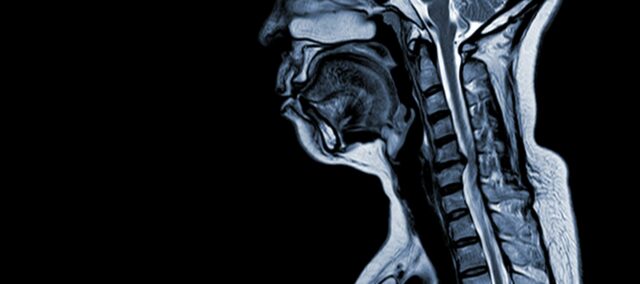

Cervikal spondylotisk myelopati (CSM) er en nevrologisk tilstand som er den viktigste årsaken til ryggmargsskade hos voksne. Enkelt sagt involverer det kompresjon eller skade av ryggmargen i nakken, først og fremst på grunn av den naturlige aldringsprosessen som påvirker nakkevirvlene. Begrepet "myelopati" stammer fra de greske ordene "myelon", som betyr "ryggmarg" og "patos", som betyr "sykdom".

- Diskdegenerasjon (utbulende plate) : CSM begynner ofte med degenerasjon av mellomvirvelskiver i cervikal ryggraden, noe som får dem til å bule eller stikke ut i ryggmargskanalen.

- Subperiosteal beinformasjon (ventral til spinalkanal) : Som svar på økt mekanisk stress, danner kroppen nytt beinvev på forsiden (ventrale) siden av ryggmargen, noe som potensielt begrenser plassen for ryggmargen.

- Ossifikasjon av bakre langsgående ligament: Det bakre langsgående ligamentet kan gjennomgå ossifikasjon, herding og forkalkning, noe som bidrar til innsnevring av ryggmargskanalen.

- Hypertrofi av Ligamentum Flavum: Hypertrofi av Ligamentum Flavum fører til at den tykner og blir mindre fleksibel, noe som ytterligere griper inn i rommet i ryggmargen og komprimerer ryggmargen.

Disse strukturelle endringene fører samlet til kompresjon og innsnevring av ryggmargskanalen, noe som resulterer i kjennetegnssymptomer og komplikasjoner forbundet med CSM. Å gjenkjenne disse risikofaktorene og forstå de patofysiologiske mekanismene som er involvert er avgjørende for både forebygging og behandling. Tidlig diagnose og passende intervensjoner er avgjørende for å dempe effekten av disse strukturelle endringene på ryggmargen.